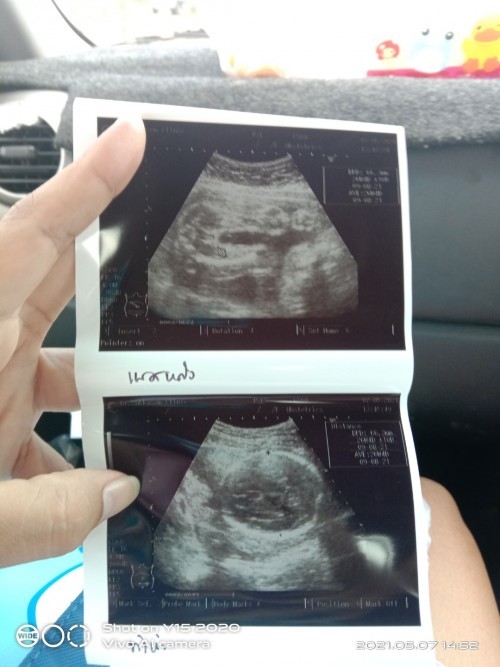

แม่! 🤰💖อวดรูปอัลตร้าซาวด์กัน

โชว์รูปแรกของเบบี้กันหน่อยน้า เพศหญิง👧หรือชาย🧑เอ่ยยย 😍🥰💜 17/09/2563

ผู้หญิงค่ะ 14วีค

หญิงคะซาวก่อนคลอด2อาทิต

กำหนด1สิงหา เพศหญิงค่ะ🥰

ยังไม่รู้เลยคร่าาา🥰🥰🥰